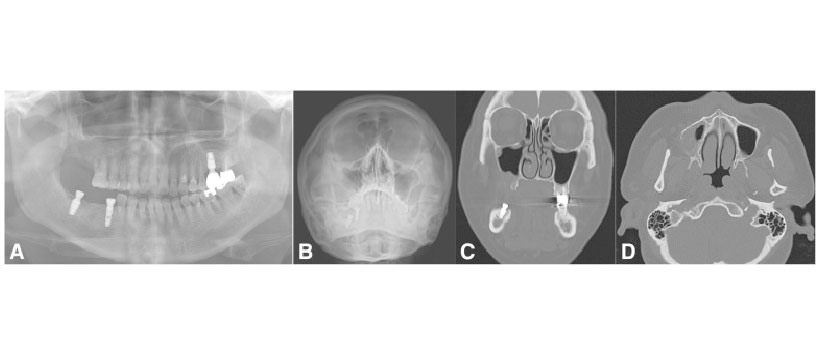

Figura 3: La fístula oronasal crónica después de la extracción del segundo molar con varios puntos de reabsorción ósea alveolar indica sinusitis maxilar odontogénica. Vistas panorámicas preoperatorias (a), de Water (b), TC coronal (c) y TC axial (d)

Complementando a los sintomes es necesario realizar una exploracion con examenes por imágenes, desde una radiografìa periapical, radiografìa panoramica y radiografìa de Waters donde se muestre la discontinuidad del piso y la opacificación del seno maxilar hasta afectado hasta la endoscopia o tomografìa computarizada para valorar la extensión y el origen real de la infección. Es importante tambièn diagnosticar una problable comunicación bucosinusal post extracción dental para un adecuado tratamiento.

La incidencia de Sinusitis Maxilar Odontogénica es mucho más alta de lo que se informó en algunos antecedentes,. Aunque la etiopatogenia exacta aún es incierta, se sabe que las causas comunes son infecciones dentales e iatrogénicas. Un seno maxilar infectado con comunicación a los elementos dentales de origen puede demostrar la formación de materia purulenta y debe comprobarse primero. Las investigaciones endoscópicas y radiológicas tempranas realizadas por otorrinolaringólogos deben ser seguidas por dentistas con diagnósticos intraorales realizados con vistas panorámicas, de Water y tomografìa computarizada.